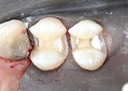

Matt Dodson #30 try in